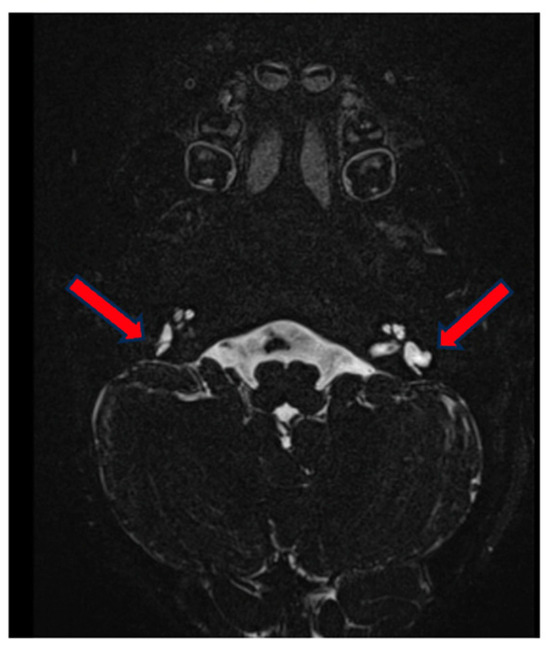

3.1. Case 1

3.2. Case 2

3.3. Case 3